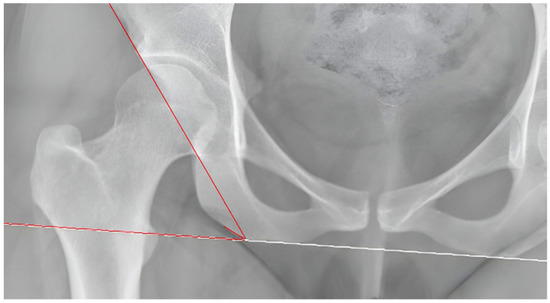

2.2. Measurements

| Femoral Inclination | 128.46° ± 7.16° (127.22°–129.70°) | 129.95° ± 6.86° (128.61°–131.29°) | 0.107 |